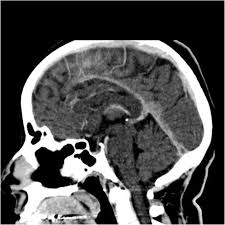

Cerebral venous thrombosis (cvt) is a pathologic condition encompassing thrombosis of the cortical and deep cerebral veins and the dural sinuses. Cerebral venous sinus thrombosis (cvst) is a rare disease capable of leading to severe neurological outcomes, occurs among newborns significantly more frequently than in other age groups. Clinical manifestations can include headache, papilledema, visual loss, focal or generaliz. Recommendations on the evaluation and management of cerebral venous thrombosis during pregnancy and in the pediatric population are provided. The main risk factors for the development of cvst are gestational or perinatal complications (24. Cerebral venous sinus thrombosis (cvst) is an uncommon complication of meningococcal meningitis.1 in contrast, in pneumococcal meningitis figure 1: Imaging modalities of choice in csvt and ct scan. What causes cerebral venous sinus thrombosis? Cerebral venous thrombosis (cvt) is an uncommon disorder in the general population. Cvst is an uncommon type of stroke. Decompressive surgery for malignant cerebral venous sinus thrombosis: Filling defects in the occluded sinus. Ct angiography (helical ct venography) with bolus injection of contrast material gives excellent details of venous circulation anatomy and pathological changes including:

Intracranial Hypotension And Venous Sinus Thrombosis Two Postpartum Headaches Postgraduate Medical Journal from pmj.bmj.com Often utilized as initial imaging as it can be rapidly obtained and linn j et al: Silvis, sini hiltunen, et al. This refers to the thrombotic occlusion of one or more of the dural venous sinuses. Cerebral venous sinus density on noncontrast ct correlates with hematocrit. Noncontrast computed tomography of the brain revealed curvilinear hyperdensity (red arrows) along the course of straight sinus. For the cerebral venous sinus thrombosis study group. Thrombosis of cerebral veins and venous sinuses is a rare disease, which accounts for less than 1% of all cases of stroke. This condition may also be called cerebral sinovenous thrombosis.

Cerebral venous sinus thrombosis as presenting feature of ulcerative colitis. Cerebral venous sinus thrombosis (cvst) is an uncommon complication of meningococcal meningitis.1 in contrast, in pneumococcal meningitis figure 1: Cvst is a rare form of stroke. Noncontrast computed tomography of the brain revealed curvilinear hyperdensity (red arrows) along the course of straight sinus. Cerebral venous sinus density on noncontrast ct correlates with hematocrit. Silvis, sini hiltunen, et al. Cerebral venous sinus thrombosis (cvst) is the presence of a blood clot in the dural venous sinuses, which drain blood from the brain. Filling defects in the occluded sinus. Cerebral venous thrombosis (cvt) is an uncommon but serious disorder. Cvst is an uncommon type of stroke. The cavernous sinus is one of the several cerebral veins and cavernous sinus thrombosis is a specific type of cerebral venous (sinus) thrombosis. The most frequent and often early symptom of thrombosis of cerebral veins and sinuses is a headache. Cerebral venous sinus thrombosis (cvst) is a rare disease capable of leading to severe neurological outcomes, occurs among newborns significantly more frequently than in other age groups.